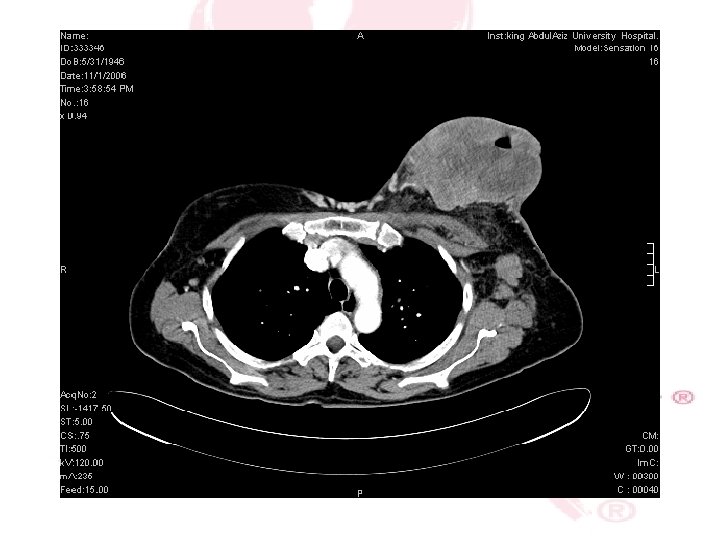

CT SCAN CHEST , ABDOMEN &PELVIS